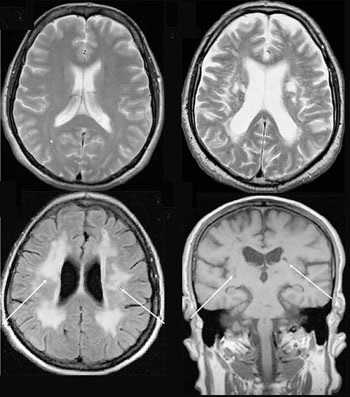

Существенное преимущество МР-томографии перед КТ заключается в том, что она не противопоказана беременным во II и III триместре и совершенно безопасна для детей. В МРТ исследуемая область сканируется в трех проекциях, что позволяет врачу-рентгенологу в полной мере оценить состояние тканей и органов исследуемой области, а высокая контрастность изображения и пространственное разрешение позволяют визуализировать серое и белое вещество головного мозга, оценивать состояние костного мозга и мягких тканей различной локализации. Кроме того, метод МРТ позволяет получать изображения сосудов головного мозга и сосудов шеи без введения контрастного препарата.

Мы также всегда делаем КТ пациентам с подозрением на нарушение мозгового кровообращения, исследование позволяет не только подтвердить диагноз, но и оценить «масштаб» поражения и выработать верную тактику. Назначают его при патологии почек, в частности, при наличии камней. На томографе можно увидеть их расположение, оценить плотность и структуру, а значит, принять решение об операции или выборе консервативных методов. МРТ имеет преимущества при изучении патологий суставов, для диагностики заболеваний головного мозга, спинного мозга, органов малого таза.